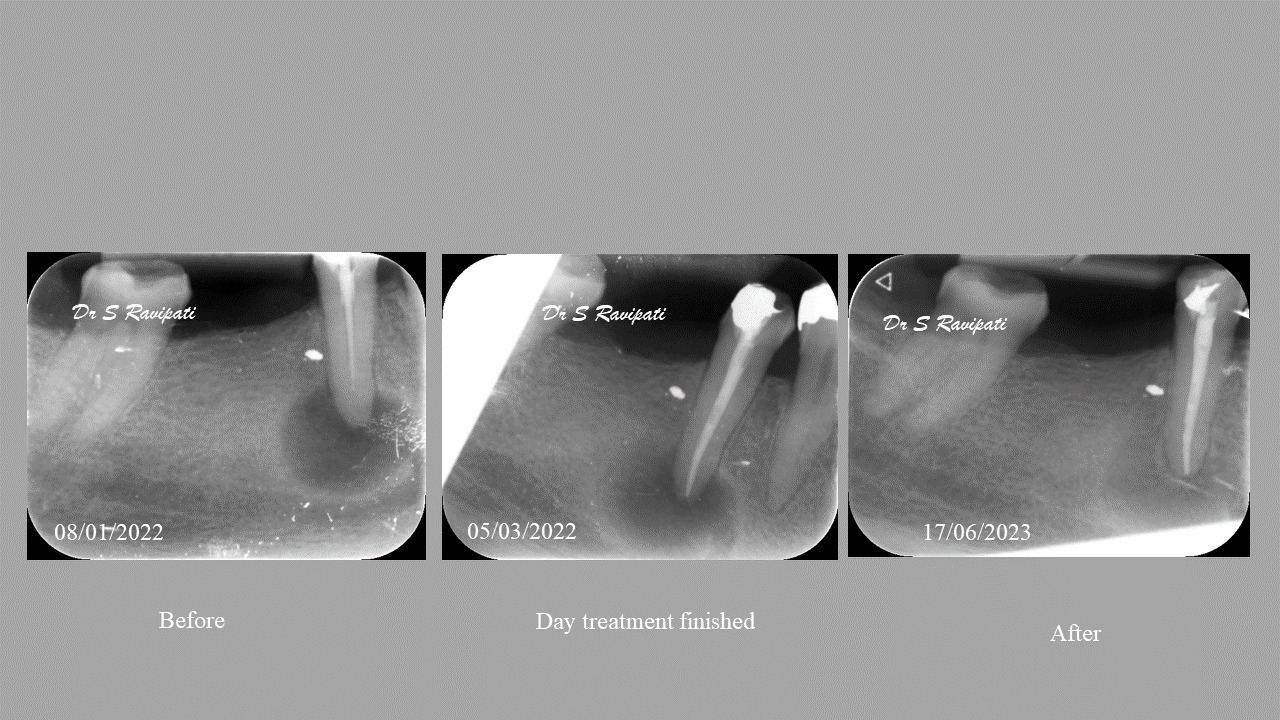

During the consultation, the dentist will first listen to your concerns and carry out appropriate tests to identify the right tooth that is causing pain. As a part of the diagnosis, your dentist will carry out various clinical tests to identify the right tooth and will take some radiographs which can aid in the diagnosis.

Studies have shown thorough cleaning with instruments, disinfection and sealing the canals contribute to the successful healing of the infection and this success is reported as 95%.